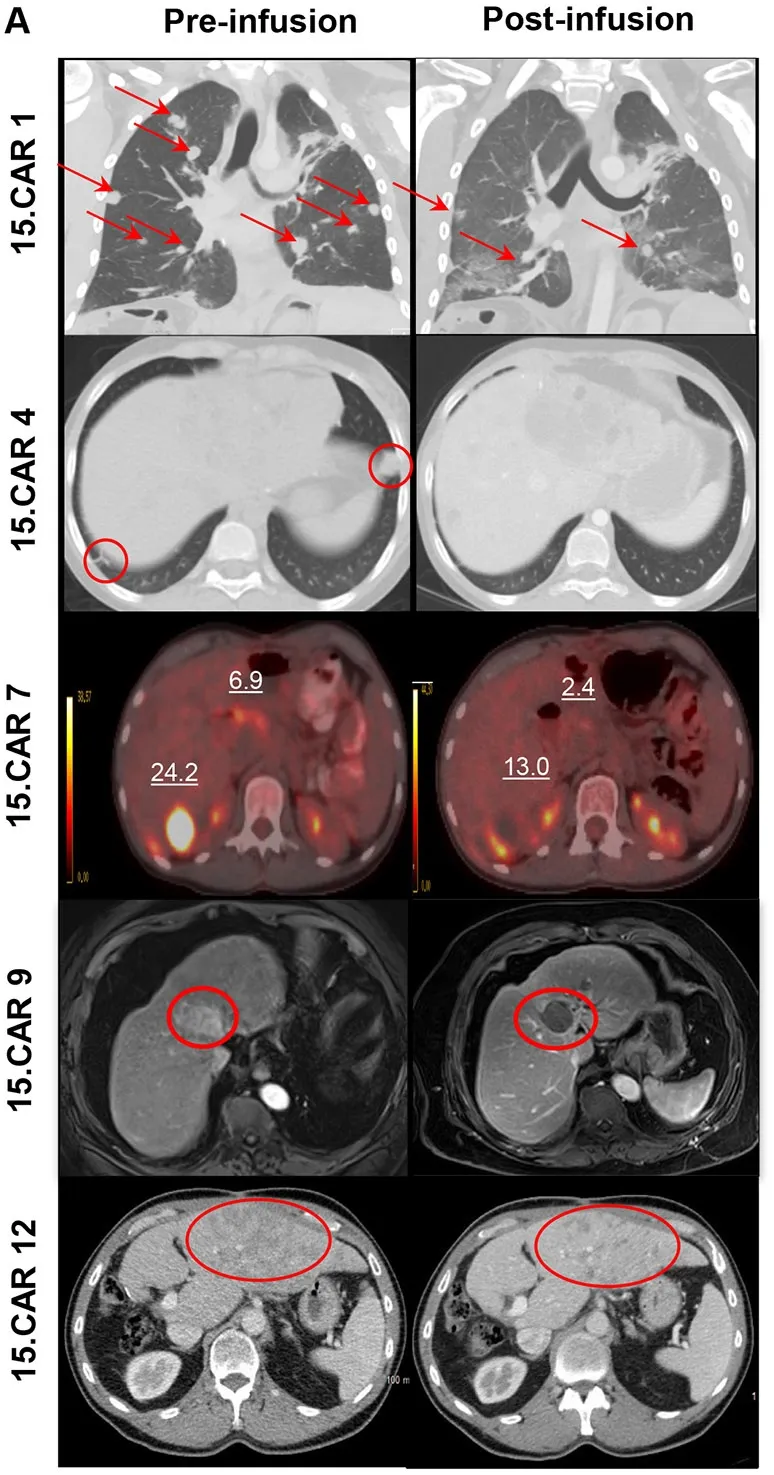

结果显示:该疗法显著促进细胞扩增,在3×10⁷个CAR-T细胞/m²(DL2)剂量组中,6例常规GPC3-CAR-T治疗患者均无客观缓解(3例达病情稳定SD);而12例15.CAR-T治疗患者中,4例达SD、4例达到部分缓解(PR)。接受15.CART细胞治疗的患者疾病控制率(DCR)达66%(8/12),客观缓解率(ORR)达33.3%(4/12),其中4号、10号患者肿瘤负荷减少超26%,7号患者残余肿块缩小约12.8%(详见下图B),PET显像显示病灶摄取显著降低,虽未达RECIST缓解标准,但明确体现抗肿瘤活性;另有2例肿瘤分泌AFP的有效患者,其AFP水平均显著下降(相关影像数据详见下图A)。值得关注的是,15.CAR9号患者经MRI检查显示肝脏肿瘤完全坏死,影像引导下病灶取样进一步证实原发性肝脏肿瘤近乎完全坏死。